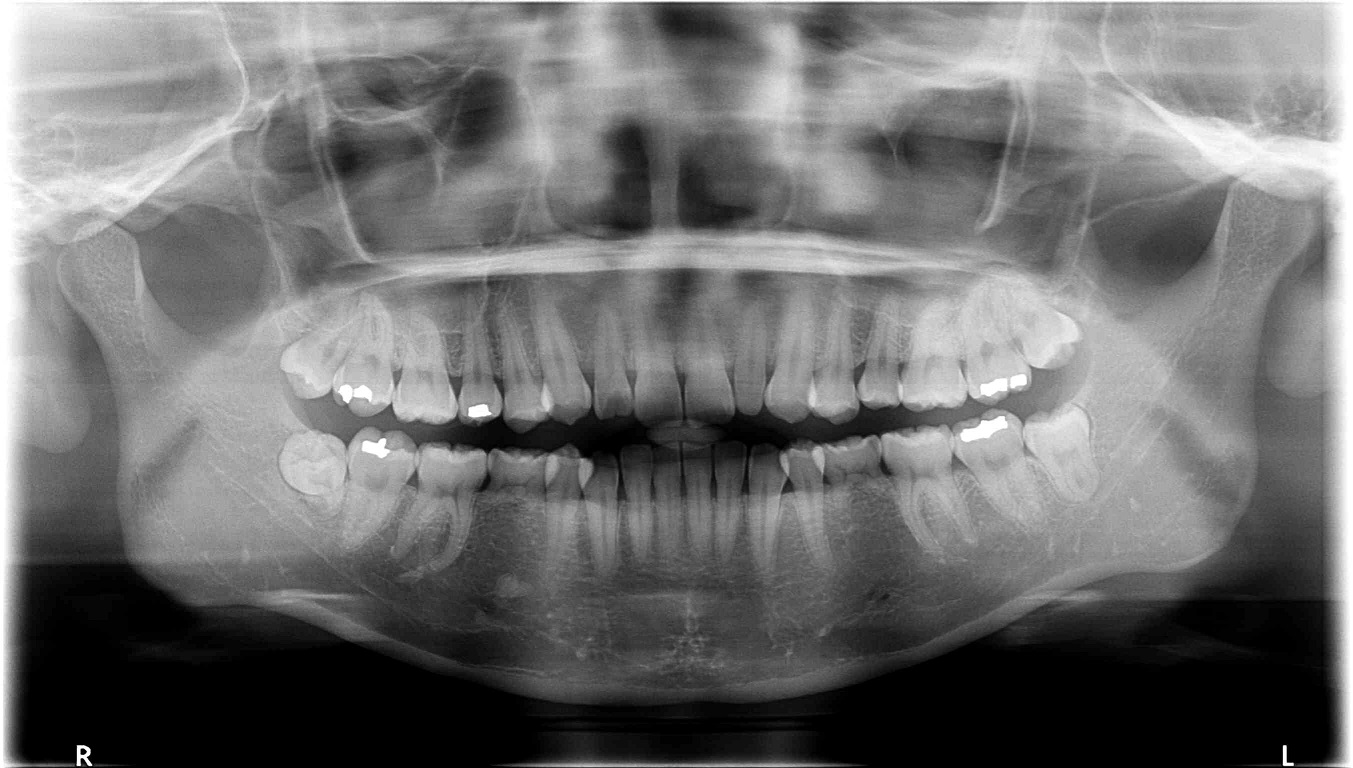

우선 저는 성인이구요(20대 후반) 사진에서 보이다시피 아래쪽에 유치가 두개 있는 상태입니다.

이걸 임플란트를 할지 교정으로 이를 밀어버릴지 고민이예요. 임플란트로만 처리한다면 더 오래 유치를 가지고 있어도 되겠지만... 입도 좀 튀어나온지라 어차피 이에 손을 대야 한다면 교정으로 돌출도 집어넣고 아래쪽 이도 교정을 할까 하거든요. (아래쪽 치열도 좀 삐뚤빼뚤해지고 있어요 ^^::)

윗니는 어차피 두개 발치하고 한다고 하시는데 아래쪽 유치가 가장 고민이네요. 조언좀 부탁드립니다 ^^ (사진 첨부했으니 함께 봐주시면 감사하겠습니다 ㅠㅠ)

덧붙여...두번째 간 치과에서는 위쪽 송곳니 하나가 왜소치아라고 하시면서 라미네이트를 말씀하시더라구요. 이곳에서 임플란트를 심지 않고 당기기를 해도 되겠다는 이야기를 들었구요. 그런데 성인 교정이 하도 부작용이 많다고들 하니 조심스러워집니다.